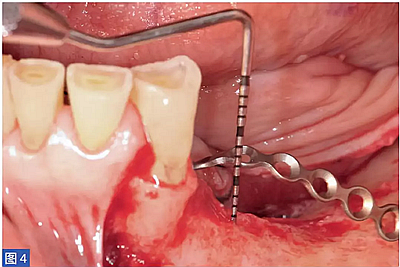

圖4:病例1. 術(shù)中內(nèi)固定鈦板。

然后用特定的微螺絲固定鈦板。當(dāng)鈦板固定穩(wěn)定后,開(kāi)始植入骨增量材料。本研究所述的6個(gè)病例中,脫蛋白牛骨骨基質(zhì)(DBBM;Bio-Oss,Geistlich)與患者自體骨結(jié)合使用。自體骨與DBBM 的比值約為50:50。骨移植物于口內(nèi)供區(qū)獲得,最好是在下頜骨升支基部區(qū)域。